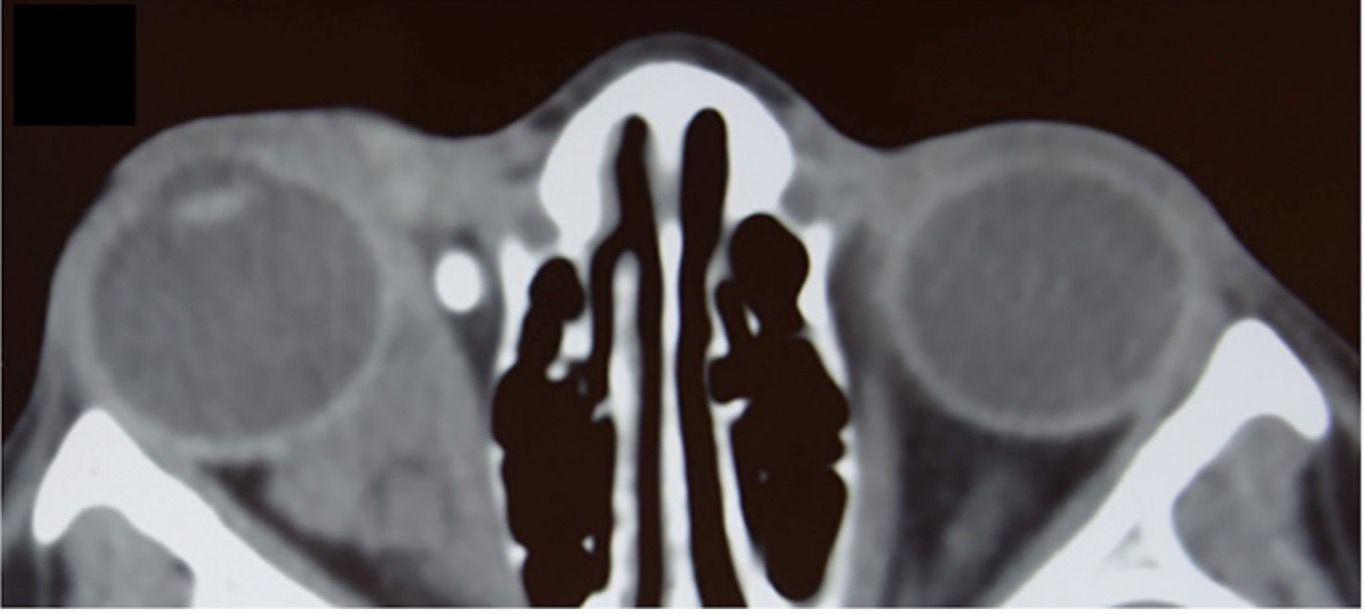

Orbital masses include a diverse spectrum of benign, malignant, inflammatory, and vascular lesions in pediatric and adult patients. Accurately diagnosing the type of lesion is critical, as management strategies differ significantly. Advanced imaging is therefore essential, and computed tomography (CT) is central to orbital evaluation. We reviewed the literature to synthesize evidence on CT features across common orbital pathologies and correlated imaging with clinical presentation to emphasize diagnostic relevance. CT characteristics are summarized for vascular lesions (cavernous venous malformation, lymphatic malformation), inflammatory conditions (orbital myositis, dacryoadenitis), benign lesions (dermoid cyst, pleomorphic adenoma), and malignant lesions (lacrimal gland lymphoma, adenoid cystic carcinoma, rhabdomyosarcoma). We present characteristic patterns of location, morphology, enhancement, and bone change, with practical discriminators and common pitfalls to aid differentiation. When used alongside clinical context, CT remains a preferred modality in many clinical settings due to its rapid acquisition, wide availability, and reliable depiction of bone and calcifications. It supports accurate diagnosis and informed management decisions in time-critical settings. This review provides a structured reference for interpreting CT findings across a wide range of orbital disease.